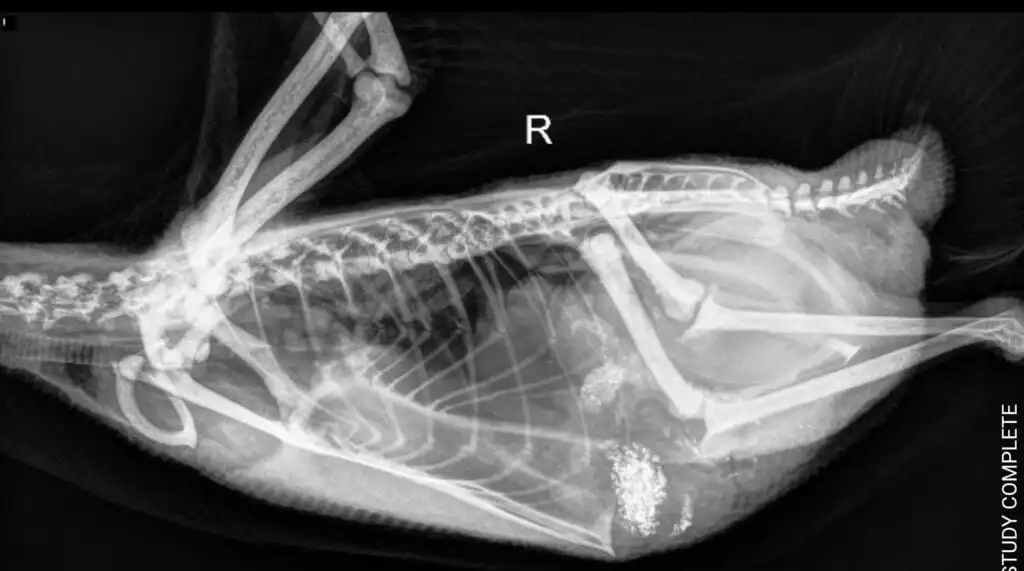

- Radiographs (X-rays): X-rays can help identify ingested metal objects within the duck’s digestive tract. This imaging technique allows the vet to locate and assess the size and position of the metal.

Despite our efforts, we faced a frustrating mystery. X-rays did not reveal any metal objects in Krümel’s digestive tract, leaving us puzzled about the source of her high zinc levels. We suspect that she may have ingested something containing zinc or another metal, but we couldn’t pinpoint the exact cause.